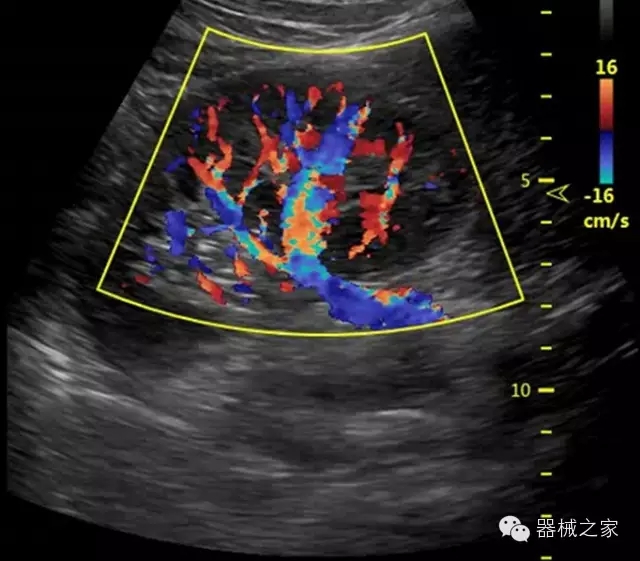

臨床圖片賞析